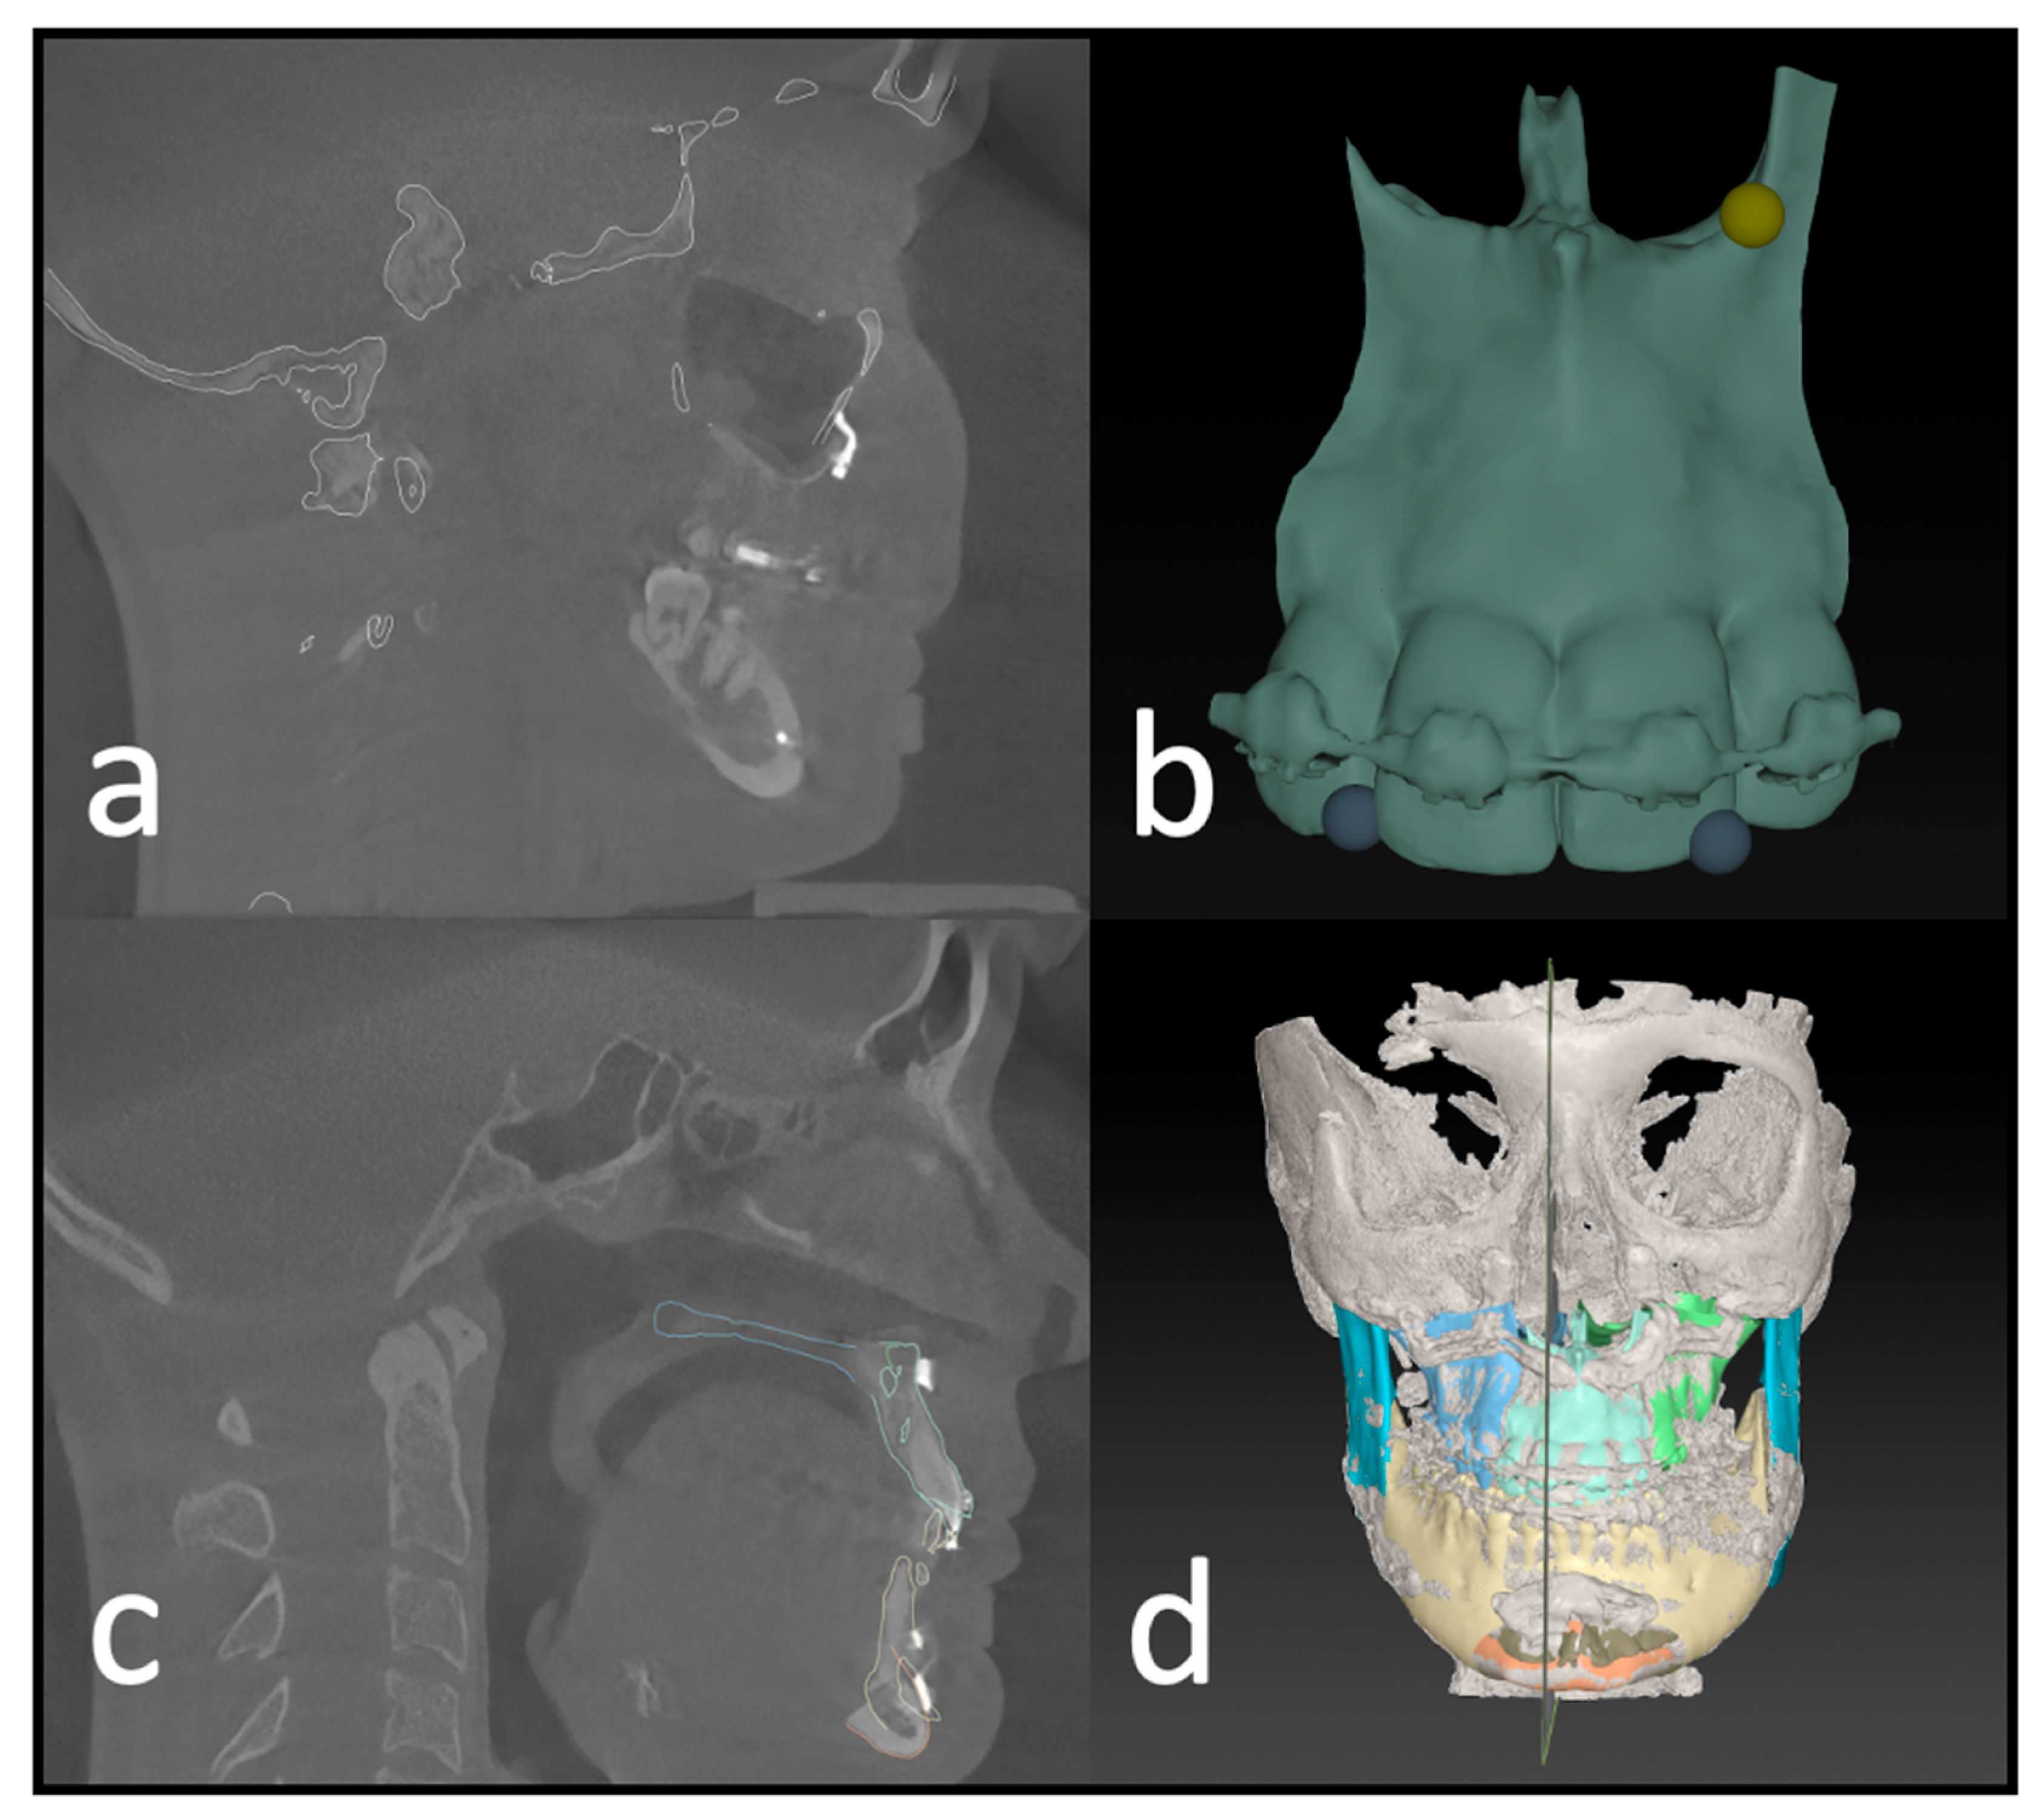

Each patient received a low-dose CT (Siemens Somatom Definition AS 64) scan of the skull before surgery (T1) and a CBCT scan approximately three days after surgery (T2) for postoperative control. We used the Orthophos SL (98 kV at 3 × 108 mA pulsed mode, spherical volume of 15.4 cm, scan time of 14 s, isotopic voxel size of 0.25 mm, Sirona, Bensheim, Germany) for the postoperative images. The preparation of the surgical planning files per our department’s routine protocols was as described by Swennen [12]. In addition to standardized photo documentation to record the natural head position, intraoral scans as *.stl files (“standard triangle language”) (Primescan, Dentsply Sirona, Bensheim, Germany) and a wax bite to register the centric condylar position were also taken. After manual adjustment of the target occlusion using the 3D-printed patient models (Modelresin, Form 3B+, Formlabs GmbH, Berlin, Germany), these target occlusions were re-digitized back into an *.stl file using a model scanner (Shining 3D EinScan-SE, Hangzhou, China) (Figure 2).

Figure 2. Workflow without dental impressions. (a) Intraoral scan with a wax bite. (b) Digital scan and registration. (c) Re-digitalization using a surface scanner. (d) Fused scan and CT for virtual surgical planning.